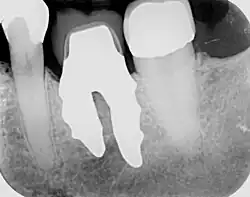

RAIs are custom made to perfectly fit the tooth socket of a specific patient immediately after tooth extraction. Therefore every implant is unique. As an optimised root-form it is much more than a simple 1:1 replica of a tooth. Since it exactly fills the gap left after the tooth is extracted, surgery is rarely needed. The implant can be produced from a copy of the extracted tooth, an impression of the tooth socket, or from a CT scan or CBCT scan.[7] The advantage of a CBCT scan is that the implant can be produced before extraction. With the former methods, it takes one or two days to fabricate an implant.

A root analogue implant can be fabricated from zirconium dioxide (zirconia) or titanium.[8] Successful titanium RAIs have been three-dimensionally printed as porous one-piece implants, using CAD software.[9] However, zirconia is the preferred material, because it is more esthetic in colour, with no grey discolouration visible through gums.[10][5]

- Natural form: a custom milled anatomic implant replicates the natural form of a tooth, so it simply fits into the tooth socket. Like the original tooth, a root analogue implant can have single- and multi-rooted forms.